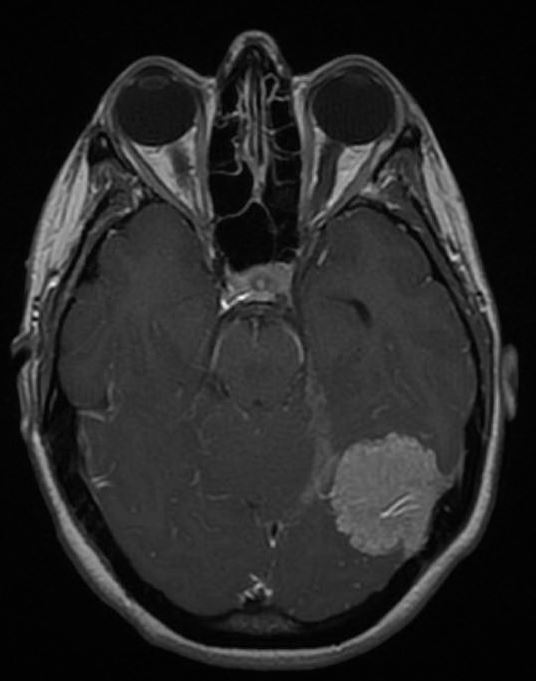

脑膜瘤严重吗?脑膜瘤起源于蛛网膜细胞,它们是覆盖大脑和脊髓的薄蜘蛛网状膜内的细胞,是常见的颅脑肿瘤...

脑膜瘤严重吗?虽然其多呈良性,但如不加以治疗,脑膜瘤会给脑部施加压力,并导致并发症。良性脑膜瘤能活多久?这取决于患者的具体治疗情况...